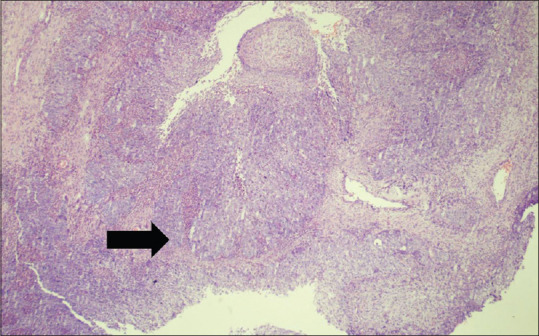

Carcinoma of the nose and paranasal sinuses is an uncommon tumour accounting for less than 1% of all malignancies and about 3% of head and neck malignancies. It is more common in fifth and sixth decades with increased male preponderance. Occupational exposure to nickel has been known to increased its occurrence. Here we present a case of 25-year male presenting with right sided nasal blockage and pain in the right eye with swelling for 2 months. Imaging studies revealed a large soft tissue density with involvement of surrounding structures with bony erosion and extension to the orbit. Histopathology and Immunohistochemistry confirmed the diagnosis of poorly differentiated sinonasal carcinoma non keratinising type.